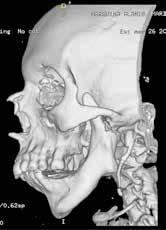

Para completar el estudio, se solicitó una tomografía axial computoriza da craneofacial (TAC) (Figura 1), dónde tras un examen exhaustivo a través de distintos cortes y reconstrucción 3D, evidenciamos una anquilosis de la ATM a la base de cráneo, desapareciendo por completo la anatomía nor mal de la ATM y su relación habitual con las distintas estructuras neurovas culares, así como la gran deformidad esquelética resultante del crecimiento y desarrollo craneofacial anormal.

Figura 1. Diagnóstico prequirúrgico del bloque anquilótico. Imágenes TAC en 3D, corte axial y corte sagital..